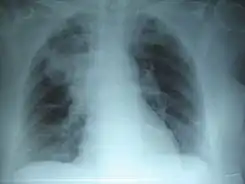

El Día Mundial de la Neumonía es una celebración anual que se lleva a cabo el 12 de noviembre desde 2009, fue establecido por la Coalición Global contra la Neumonía Infantil en ese mismo año.